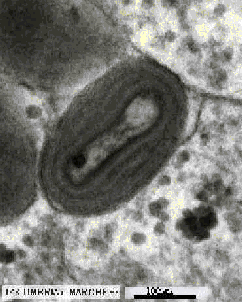

Aunque producidas por diferentes organismos y partículas, la mayor parte de las epidemias tienen unas características semejantes. Son enfermedades infecciosas originadas por la invasión del cuerpo por virus, bacterias, parásitos o partículas infecciosas como los priones. El procedimiento de invasión varia según los casos: a veces la infección nos llega por el aire, al respirar. En otra ocasiones es necesario el contacto directo con un enfermo o pueden intervenir en la propagación vectores como mosquitos o garrapatas que al alimentarse de sus víctimas les inoculan la enfermedad. Debido a esto, muchas veces las epidemias tienen un fuerte componente geográfico: por ejemplo, el paludismo suele ser una enfermedad endémica de las zonas pantanosas donde vive el mosquito Anopheles que transmite la enfermedad. En otras ocasiones la aglomeración de individuos en un espacio reducido favorece el contagio, al igual que la debilidad, el hambre u otros factores que merman o eliminan las defensas naturales del organismo.